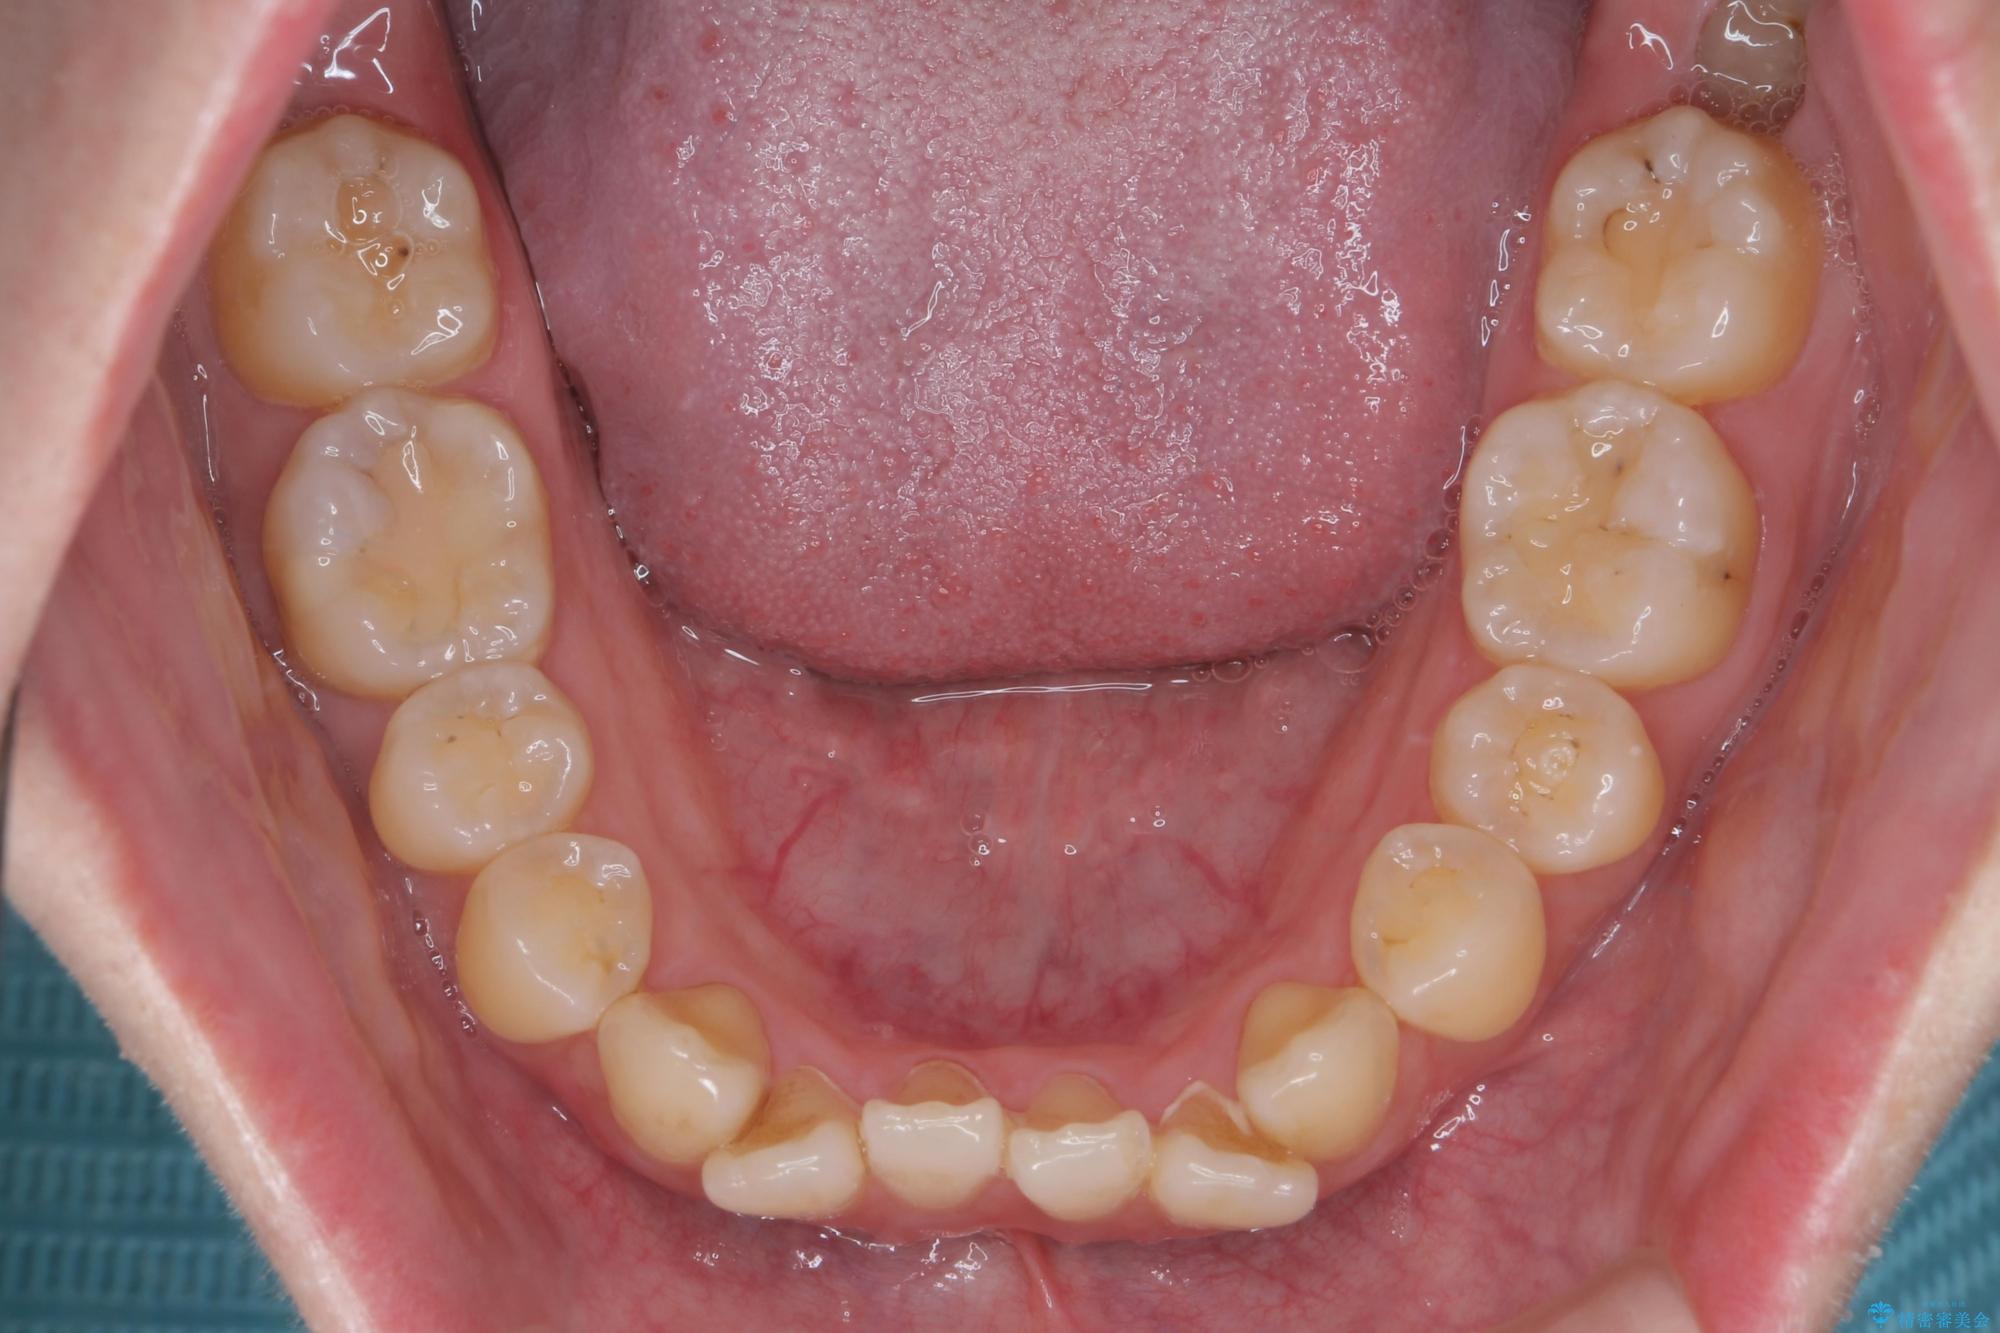

前歯のねじれが気になる、歯並びを改善したいとご来院された患者様です。

歯のねじれをきれいに取るのは、インビザライン(マウスピース矯正)だけでは難しい動きです。そのため、事前に4か月間の部分ワイヤー矯正を行い、治療期間を短くし、より美しい仕上がりを目指す計画です。